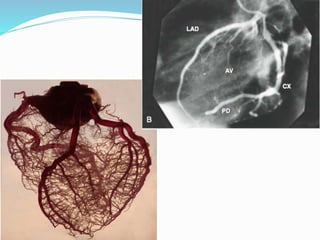

Артерии сердца

Правая коронарная артерия:

Задняя межжелудочковая ветвь

Левая коронарная артерия:

Передняя межжелудочковая ветвь

Огибающая ветвь

Артериальное кольцо (см. ниже)

Правая коронарная артерия

Левая коронарная артерия